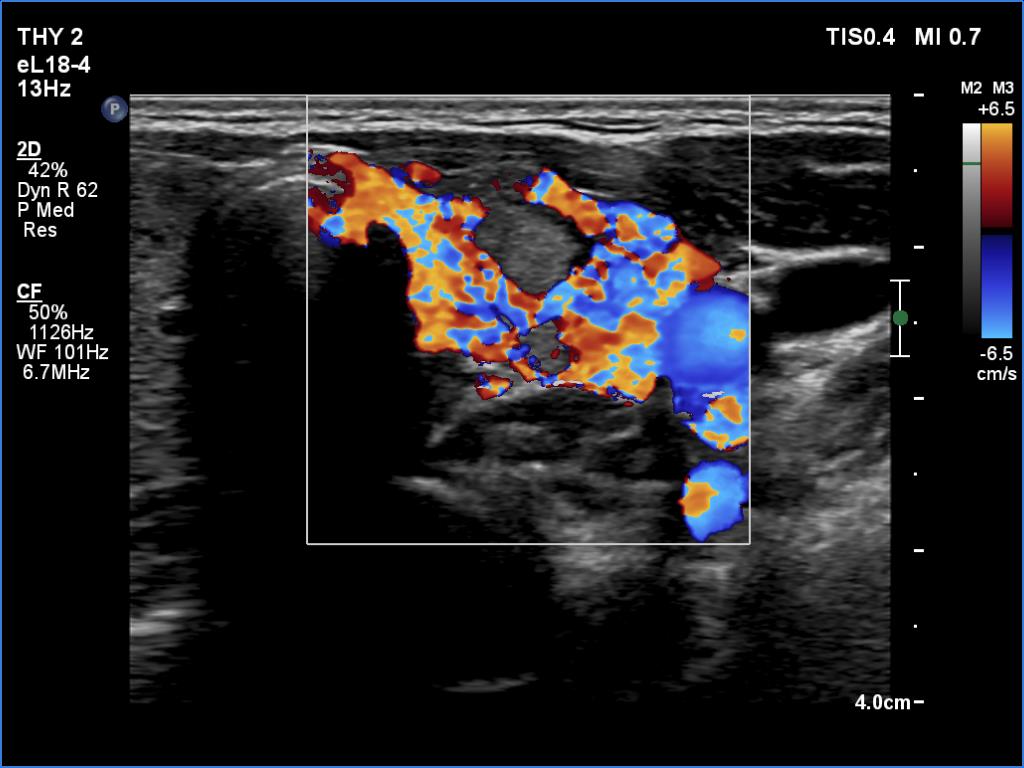

Graves' disease - case 1584

Five years after the first visit (ultrasonographic picture 8)

Left lobe, transverse scan, color Doppler mode. The vascularity is hugely increased in the extralesional part while absent in the discrete lesion.